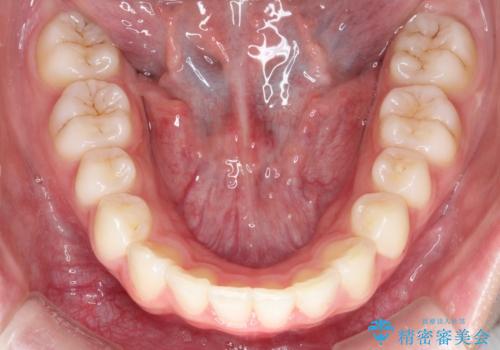

【インビザライン】出っ歯を引っ込めたい。

- 前歯の隙間と、出っ歯に見えることを主訴に来院されました。

できるだけ目立たない装置をご希望されましたので、インビザラインにて治療を行いました。

治療中は、できるだけ前歯を下げることができるように”顎間ゴム”を使用します。

”顎間ゴム”を利用することで、奥歯を後ろに動かす力を強めることができます。